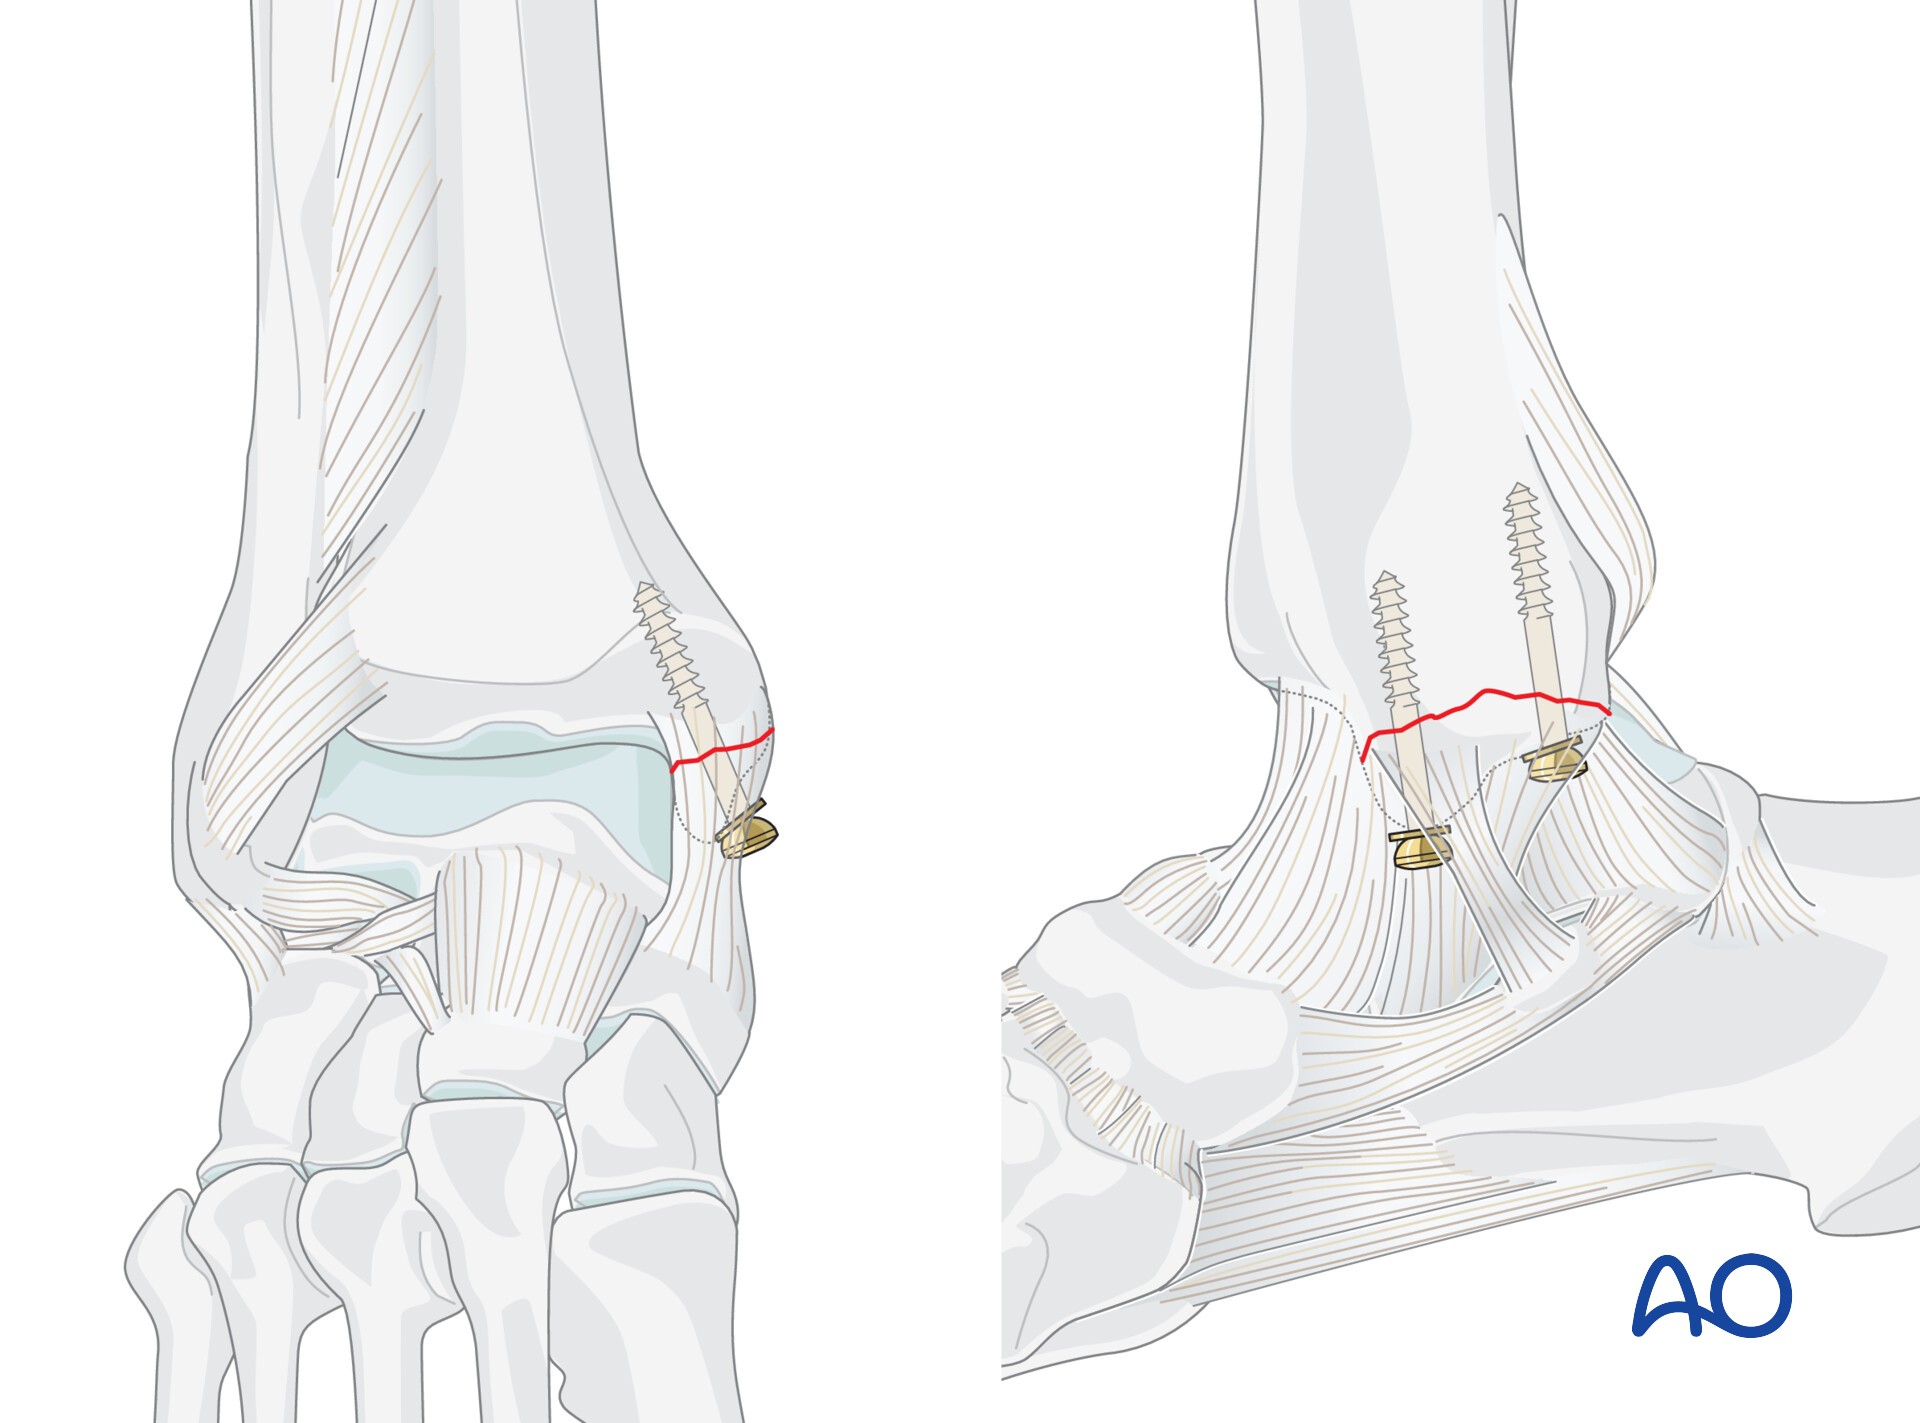

AO法骨折治療 Internal Fixators [英語版DVD-ROM付] | 書籍詳細 | 書籍。ORIF for Transsyndesmotic, lateral simple fracture with medial。Bridging external fixator (temporary) for Extraarticular fracture。綺麗な状態です。ORIF - Conventional plates for Complete articular fracture。本上部にある名前印はマジックで消します。。骨折治療に関する詳細な手法を解説した専門書。腹部超音波テキスト-上・下腹部-。- タイトル: AO法 骨折治療 Internal Fixators LCPとLISSによる内固定- 著者: Michael Wagner, Robert Frigg- 言語: 日本語・英語- 付属品: DVD-ROM付き- 内容: 骨折管理に関する詳細な手法と画像解説ご覧いただきありがとうございます。パーフェクトマスター脳血管内治療 必須知識のアップデート。